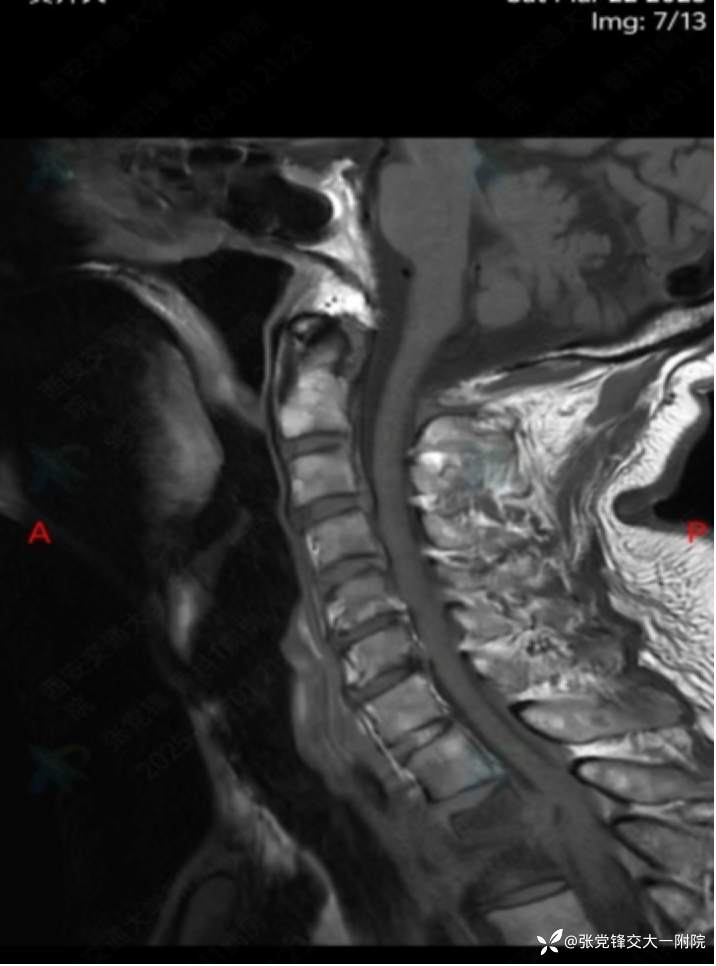

【影像学检查】

术前MRI